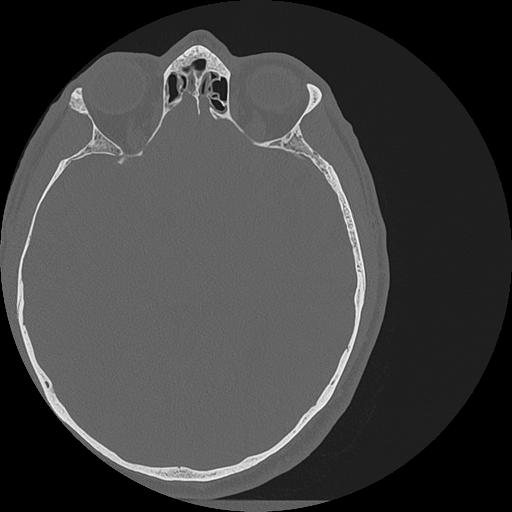

7 HUESO,,Vol,0.5,HUESO,,